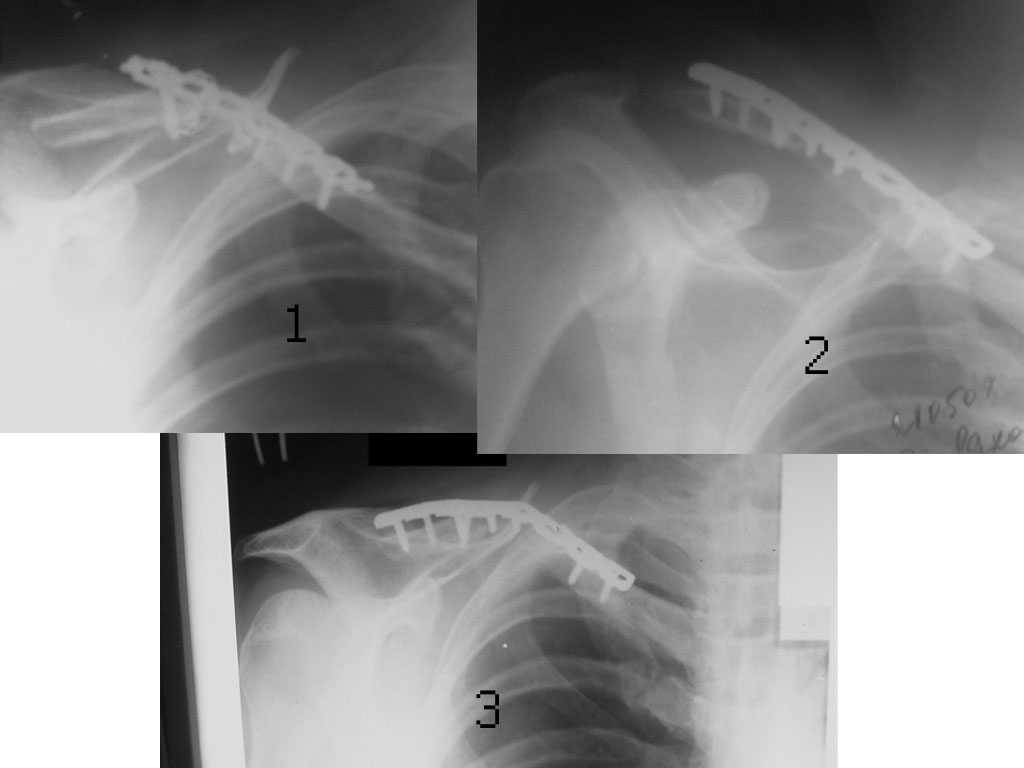

Несросшийся перелом ключицы

В отделение поступил больной, оперированный 2 мес. назад по поводу оскольчатого перелома средней трети правой ключицы. Перелом несросшийся, фиксатор несостоятелен, имеется смещение, угроза перфорации кожи. Рис. 1

Намми произведен реостеосинтез ключицы пластиной с угловой стабильностью, с замещением деффета диафиза ключицы костным аутотрансплантатом. Рис. 2

Через 5 мес. трансплантат рассосался, повторное смещение, несостоятельность импланта. Рис. 3 Ваше мнение,что делать?